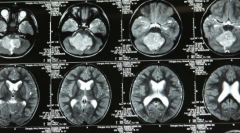

髓母细胞瘤(MB,medulloblastoma)呈双峰发病,高发年龄段一个在4~8岁之间,另一个在21~40岁之间;MB为富血供、富细胞肿瘤(另一个富细胞肿瘤为CNS淋巴瘤)...

髓母细胞瘤是后颅窝比较常见的恶性肿瘤,也是中枢神经系统恶性程度较高的神经上皮性肿瘤之一。它的细胞形态很像胚胎时期的髓母细胞,因此得名。髓母...

髓母细胞瘤是儿童时期较常见的恶性脑肿瘤,占儿童中枢神经系统肿瘤的12%~15%;在lt;15岁的儿童中,年发病率约为5/100000。髓母细胞瘤具有预后差、生长快...